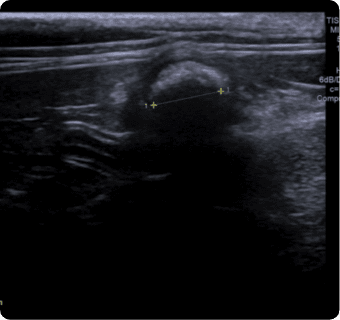

일산시티동물의료센터는 지멘스에서 개발한 고성능 프리미엄 초음파 장비인

Siemens Sequoia를 활용하여 심장, 복부 장기, 림프절 등의 구조물을 선명하게 구현하고,

미세한 해부학적 구조까지 정밀하게 확인할 수 있습니다.

또한 급성 췌장염, 급성 신부전, 자궁축농증, 방광염, 요로결석, 소화기 이물,

비장종양 등의 질환을 진단하고, 환자의 상태를 평가하는 데에도 활용됩니다.